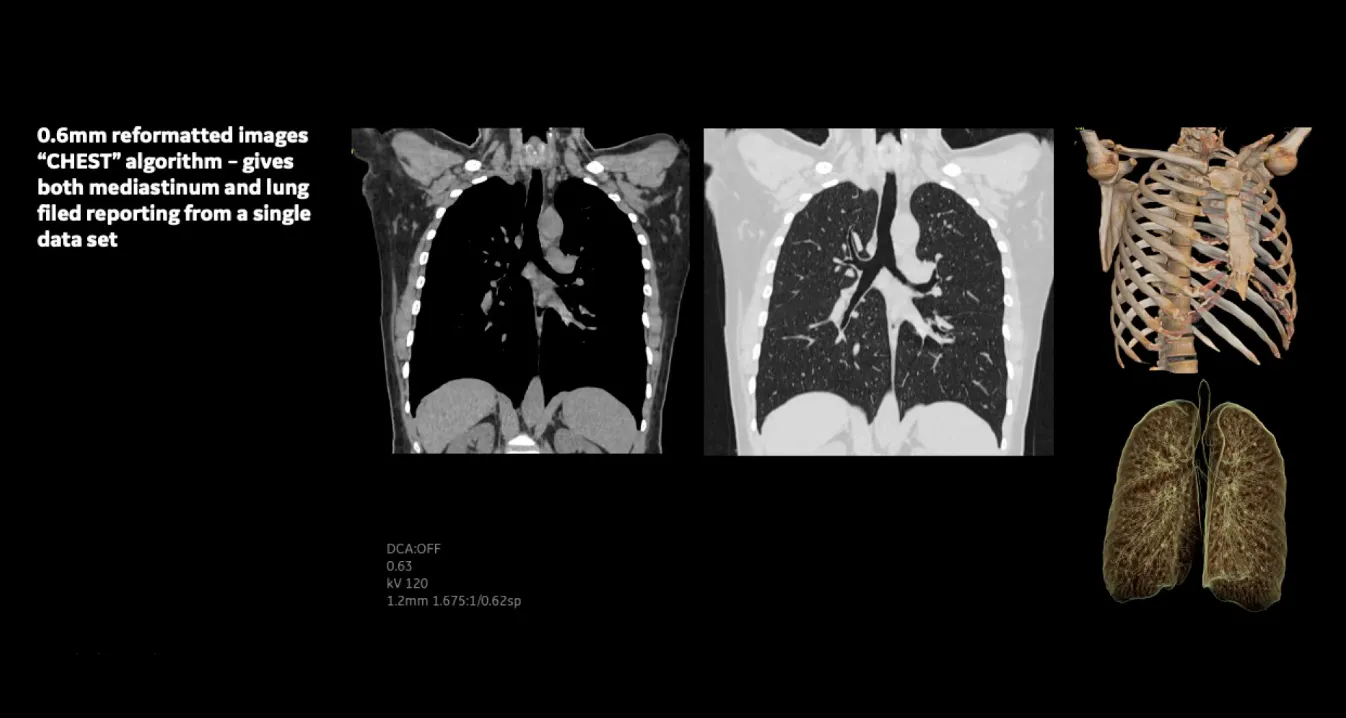

Клинические изображения

• Clarity Imaging Chain — комплексная цепочка визуализации для чётких и чистых изображений.

• IQE (Image Quality Enhancement) — улучшение качества изображения и снижение спиральных артефактов при тонких срезах.